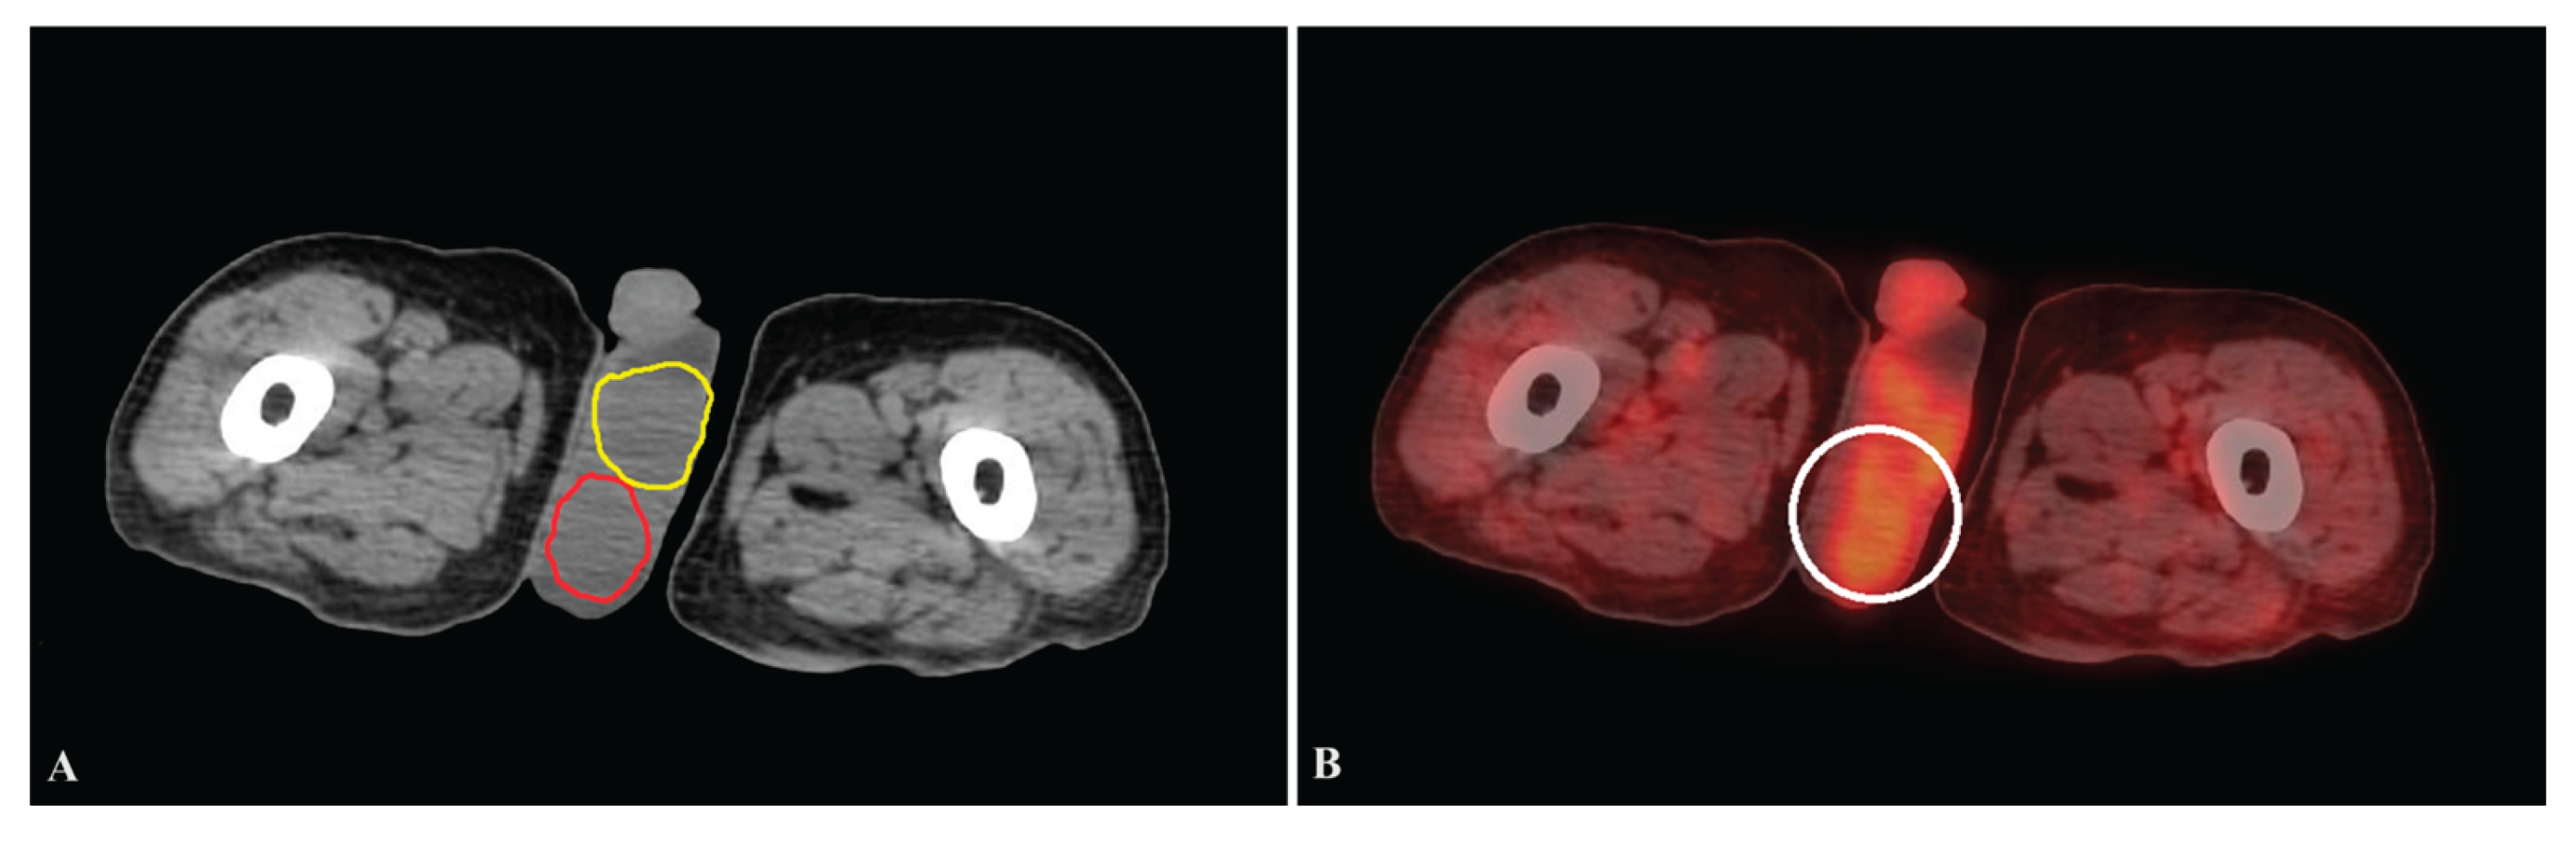

Figure 2. For each slice, a specific location inside the testis was chosen as the roi. A: Right testicular (red roi) and left testicular (yellow roi) volumes were determined by multiplying the area by the thickness of the slice. B: The mean standardized uptake value of the testis was measured by manually positioning the roi ring (white roi) on PET/CT images. roi = region of interest, PET/CT =positron emission tomography/computed tomography.

Testes were identified on low-dose CT images as oval or round soft-tissue structures (Figure 1). These structures typically exhibit density values between 30 and 50 Hounsfield units. Visual assessment and standardized region-of-interest (ROI) placement were employed instead of fixed cutoff values.

For each testis, a circular or oval ROI was placed to encompass the tissue. The total area was multiplied by the slice thickness of 5 mm to calculate volume. Testicular long axis was also recorded for reference.

PET images were used to automatically estimate the mean FDG uptake within each testicular region (Figure 2). Adjacent tissues and unrelated signals were excluded.